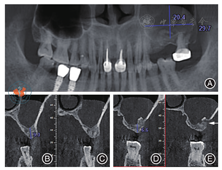

口腔卫生及25、26区牙龈状况良好,25附着龈宽约3 mm,26附着龈宽度约2.5 mm。术前CBCT示:25牙槽嵴宽约8 mm,高约9 mm,26牙槽嵴宽约7.5 mm,高约6.6 mm,左侧上颌窦内可见1个约29.7 mm × 20.4 mm,边界清楚、半圆形低密度影(图4)。

注:图4A为种植前囊肿大小;图4B~ 3C为种植前25牙槽嵴高度;图4D~ 3E为种植前26牙槽嵴高度,箭头示26颊侧骨质缺损